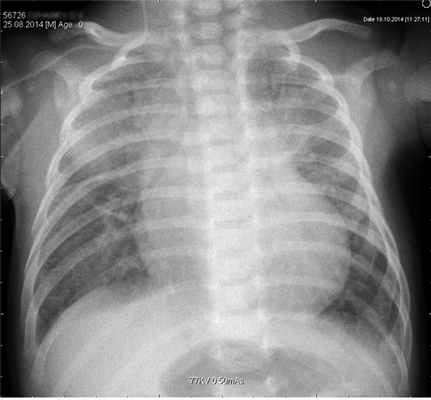

Описание рентгенологической картины при поступлении: в верхних отделах обоих легочных полей выявлены неоднородные затемнения в прикорневых отделах. Справа на фоне тени нижнего угла лопатки нельзя исключить формирование очага инфильтрации. Легочный рисунок в паракордиальных отделах правого легочного поля деформирован по крупнопетлистому типу с признаками локального вздутия легочной паренхимы — буллы? Бронхолегочная дисплазия? (рис. 1). В крови гемоглобин 105 г/л, лейкоциты 10,9·10 9 /л; п.я. 8%, с.я. 29%, лимф. 55%; СОЭ 25 мм/ч; в биохимическом анализе отмечена гипербилирубинемия за счет непрямой фракции; уровень прокальцитонина выше 10 нг/мл (норма 0—0,5 нг/мл). КЩС от 18.12: рH 7,27, рСО2 41,3 мм рт.ст., рО2 53,5 мм рт.ст., т. е. имелся респираторный ацидоз.

Рис. 1.РентгенограммаоргановгруднойклеткиребенкаД.

С учетом данных осмотра, анамнеза и результатов лабораторного обследования установлен предварительный диагноз: правосторонняя верхнедолевая аспирационная пневмония. Дыхательная недостаточность II степени. Последствия перенесенной перинатальной гипоксии центральной нервной системы. ВПС: ООО 3 мм, ОАП. Недостаточность кровообращения 2А степени. Гиперволемия малого круга кровообращения. Гипербилирубинемия. Тяжесть состояния обусловлена дыхательной недостаточностью II степени, недостаточностью кровообращения 2А степени, которая обусловлена пневмонией и ВПС. Назначены: антибактериальная терапия (меропинем); пентаглобин; инфузионная терапия, кардиотонические средства, гемотрансфузия (эритроцитная масса, свежезамороженная плазма); увлажненный кислород.